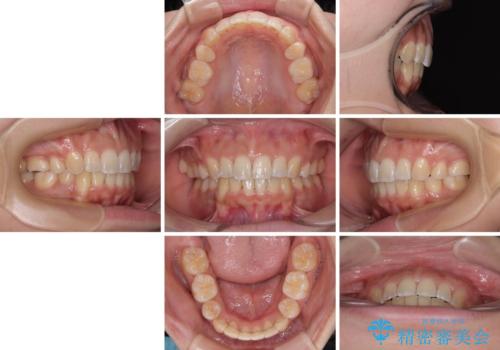

八重歯と上顎前突 ワイヤー装置での抜歯矯正

- 八重歯と、上下前歯が接触しないくらい前突した前歯を気にして来院された患者様です。

奥歯の噛み合わせは正常に近い状態でしたが、右上の奥歯に突起があったり、上下前歯が非接触であったりしていたため、補助装置を使用して上顎前歯を積極的に引っ込めるように計画しました。

口元の突出感を改善するために上下左右の小臼歯4本を抜歯し、ワイヤー装置によりデコボコを解消しながら口元の突出感も改善していくこととしました。

上下の前歯が接触する仕上がりとなったので、横顔の印象が大幅に改善されました。